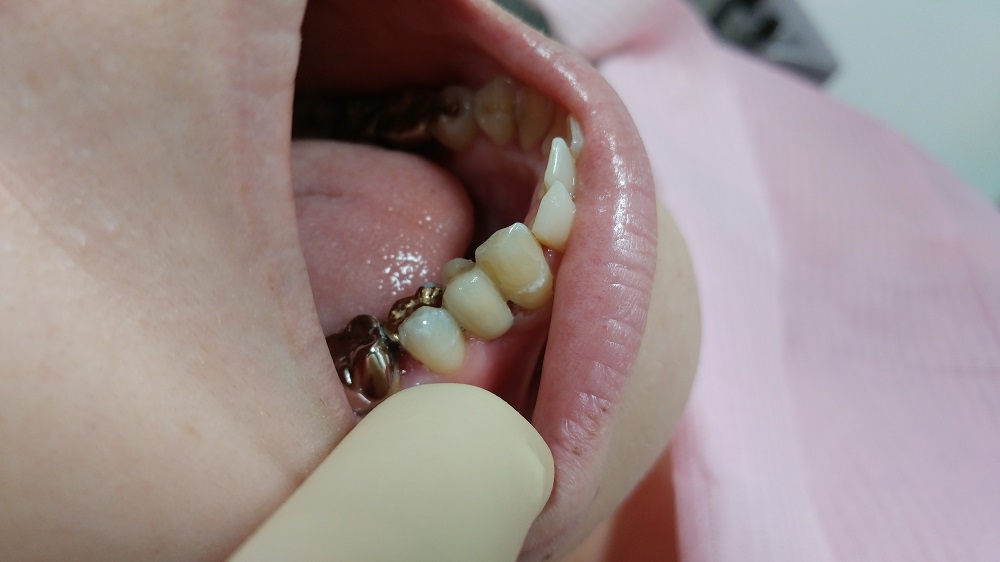

患者さんは顔出しNGだが、写真の掲載も了承してくれた

これが、抜歯した後の状態である

奥の歯には金属の詰め物(インレー)と白いレジンの詰め物が施してある

素人では判りづらいだろうが、近心側 解りやすく言えば、抜歯した1つ奥の歯の歯を抜いた側には白いセメント「レジン」が詰まっている